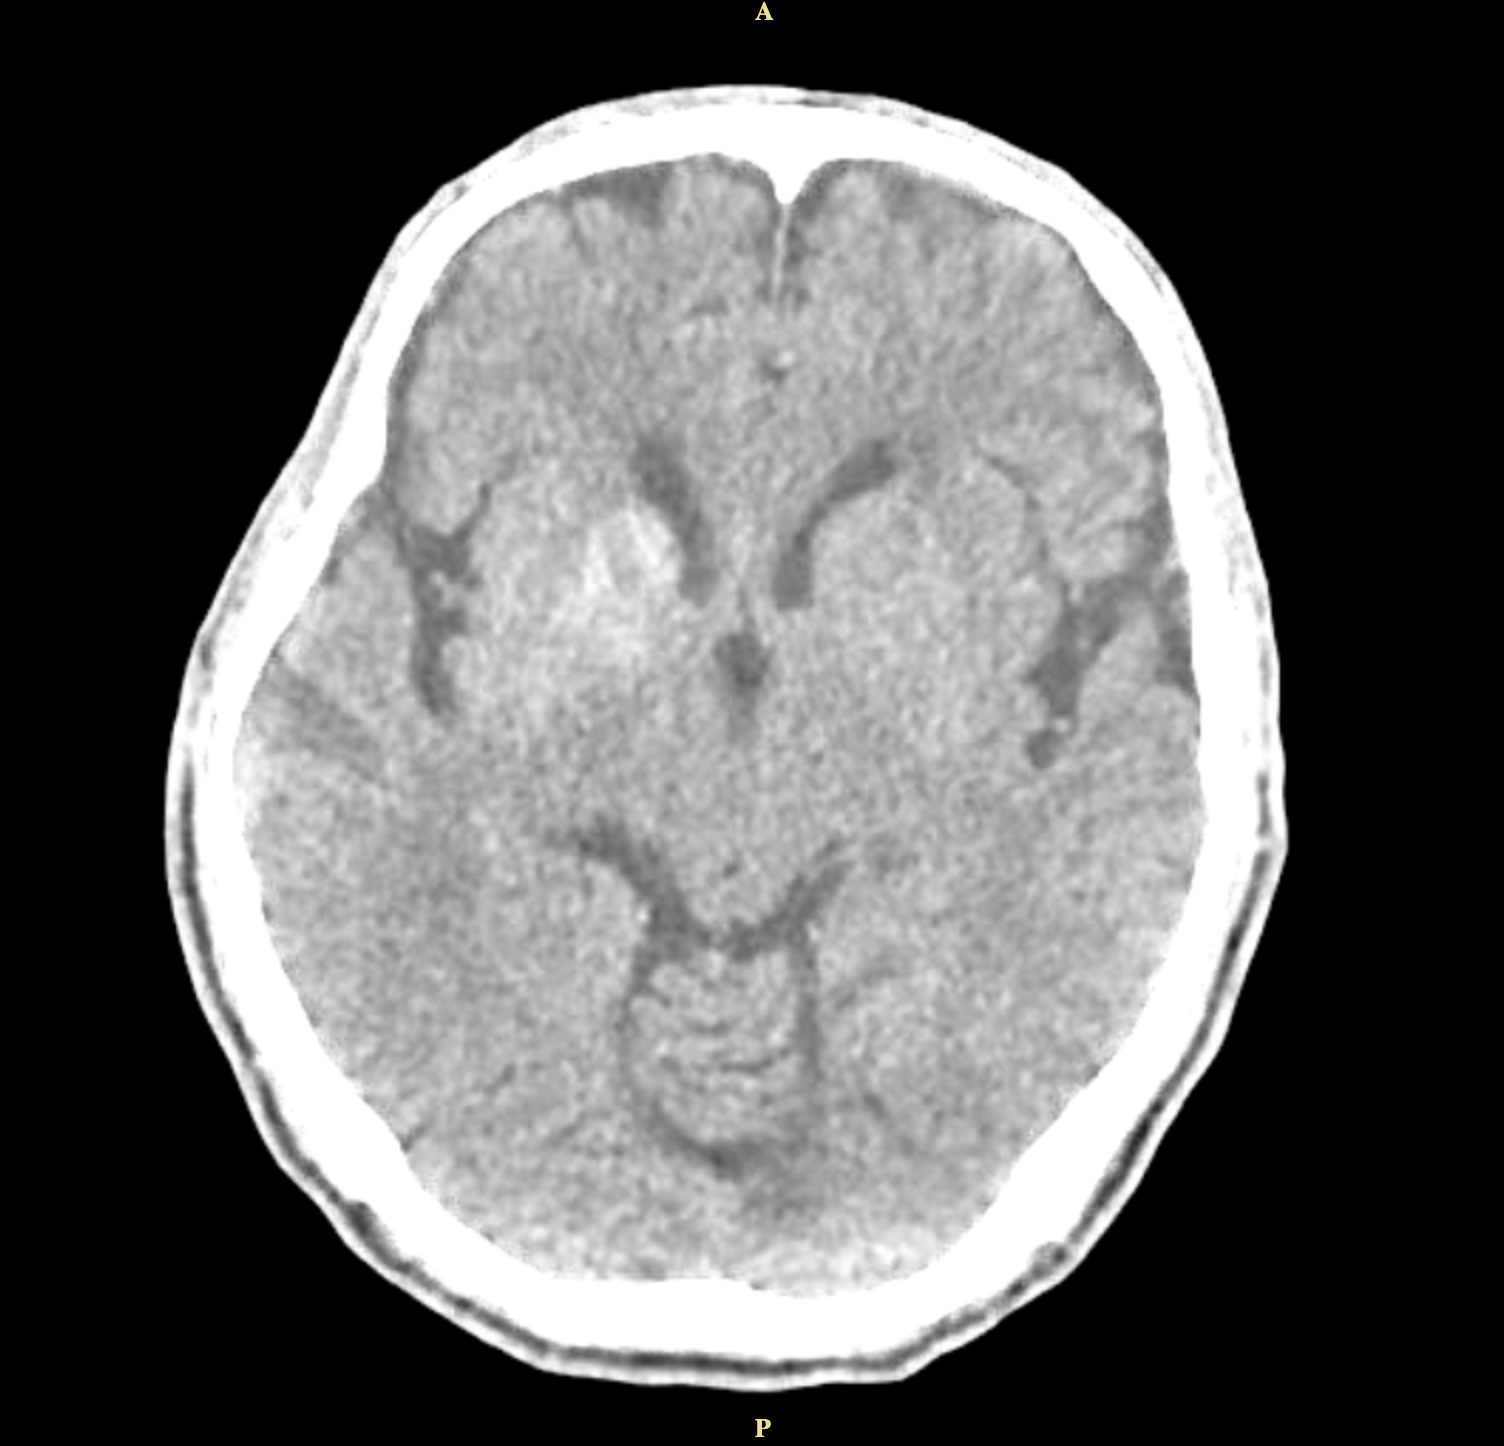

Method: A 62-year-old man with uncontrolled diabetes presented with left-sided involuntary movements and slurred speech. His blood glucose was elevated at 576mg/dl, and CT imaging showed hyperdensity in the right caudate and lentiform nuclei. His condition improved with glycemic control, and antichoreic medications were not needed.

Results: This condition occurs in about 1 in 100,000 individuals. Diagnosis relies on neuroimaging, particularly CT or MRI, which reveal basal ganglia lesions, often in the putamen or caudate nucleus. The hallmark finding is striatal hyperintensity without mass effect, sparing the internal capsule. CT has a sensitivity of 78%, and MRI 95% for detecting diabetic striatopathy, with resolution times ranging from 10 to 60 days.

Conclusion: The classic triad for diabetic striatopathy includes poor glycemic control, unilateral striatal hyperdensity on CT imaging, and contralateral choreic movements. Treatment involves achieving euglycemia and managing chorea. Symptom resolution can occur within 2–14 days, with glycemic control alone resolving symptoms in 25% of cases. Adding anti-choreic medications increases resolution to 76%. He continued intensive insulin therapy for 6 months, leading to improvement and eventual resolution of left-sided movement.

Figure 1.4